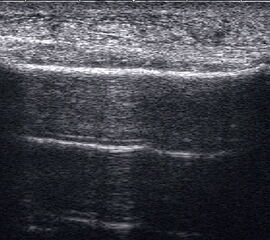

Lagerung: Bauchlage, ggf. Sprunggelenk mittels Rolle unterlagert.

Schnittführung: LS über der Achillessehne, ggf. in leichter manueller Vorspannung der Achillessehne, damit diese parallel zum Schallkopf optimal eingestelt werden kann (Abb. 52).

Referenzstruktur: Direkt unter der Haut und der dünnen Subkutis liegt echogen und straff parallel die Achillessehne mit ihrem echogenen Peritendineum (Abb. 53), Tuber calcanei.

Befunde: Da die Sehne zumeist nicht glatt, sondern bündelförmig reißt, stellen sich auch in der Sonographie anders als bei den Peroneal- und Flexorensehnen keine spargelspitzenähnlichen Rissenden dar. Echogene Rissränder, umgeben von echoarmem Hämatom sind beweisend für eine Ruptur. Risse der Achillessehne können auch nur einen Teil des Sehnenquerschnitts betreffen. Daher ist die Untersuchung verschiedener TS bedeutsam (Abb. 54 bis 56). Unter Kontrolle am Monitor kann die Diagnose in maximaler Dorsalextension klarer gestellt werden (Abb. 57).

In maximaler Plantarflexion kann versucht werden, die Sehnenstümpfe anzunähern. Für die Therapieplanung ist entscheidend, ob sich die Stümpfe der Sehne in 30° Plantarflexion in Kontakt bringen lassen. Dies ist beispielsweise Voraussetzung für eine konservative Behandlung.